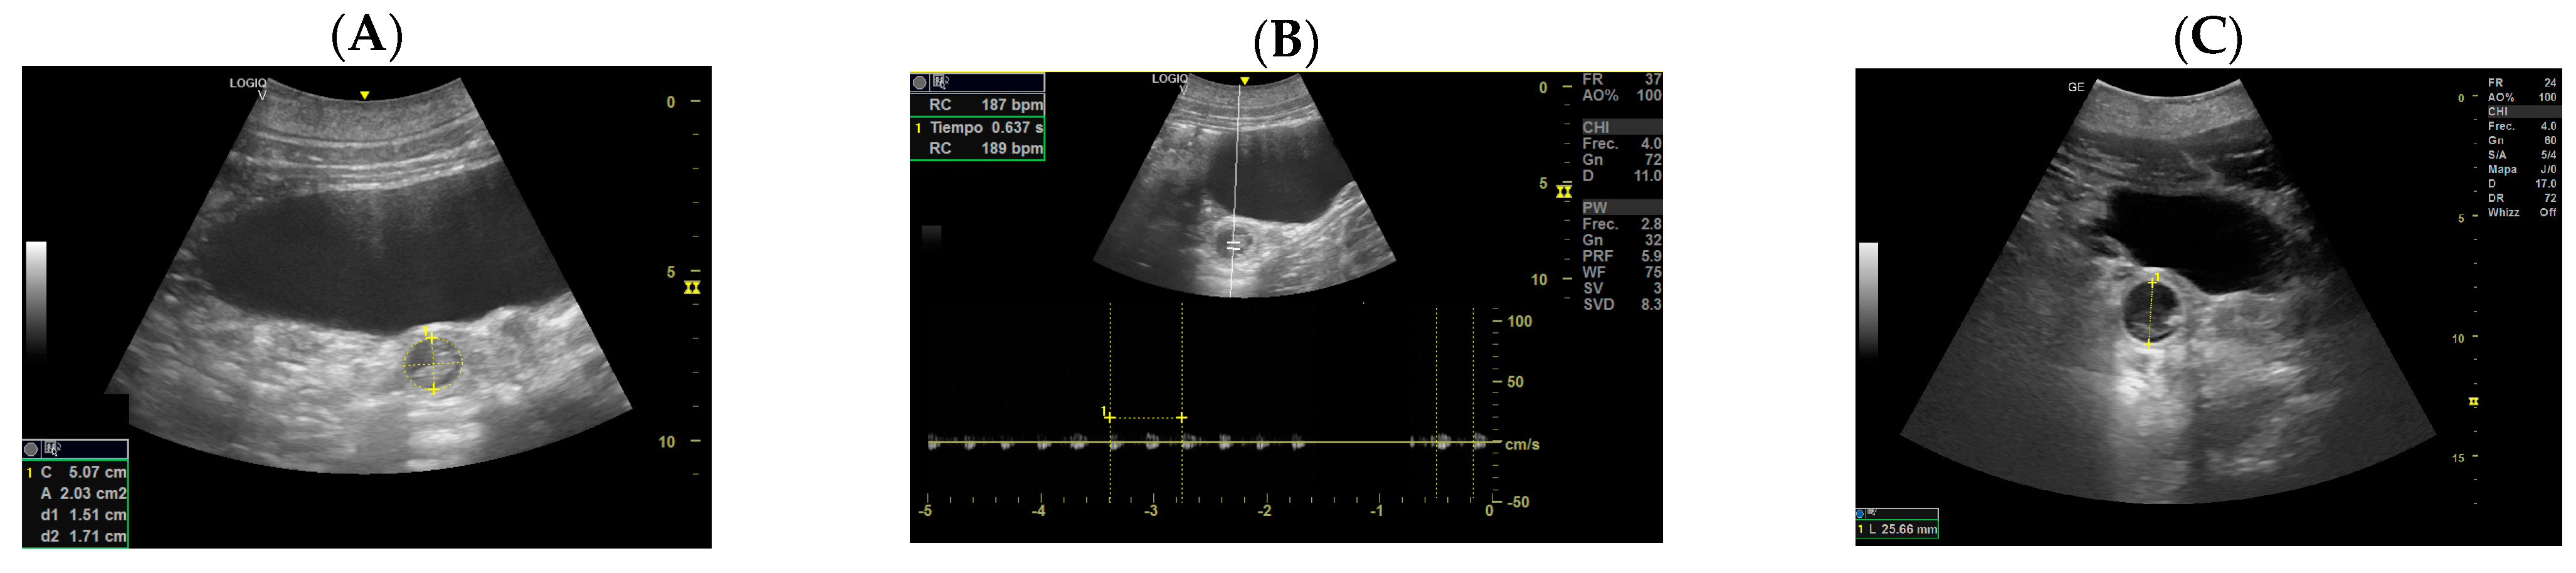

- Day 113 ± 4 post-ovulation: The embryonic vesicle was first recognizable in the uterine cavity as a roundish structure with an average diameter of 1.71 cm with an anechoic content. In addition, it is possible to recognize the embryo inside it as an elongated hyperechoic structure (Figure 2). Thanks to these findings, it has been possible to make a diagnosis of pregnancy.

- Day 129 ± 3: Embryonic cardiac mechanics is displayed, as a point of maximum fluctuation of the echoes. It is possible to recognize from the beginning of the heart rate. The heart rate was measured once the cardiac mechanics became visible and remained constant between 205 and 155 bpm until the ninth month of pregnancy. For the next 3 months, it stabilized at 140–135 bpm (Figure 3).